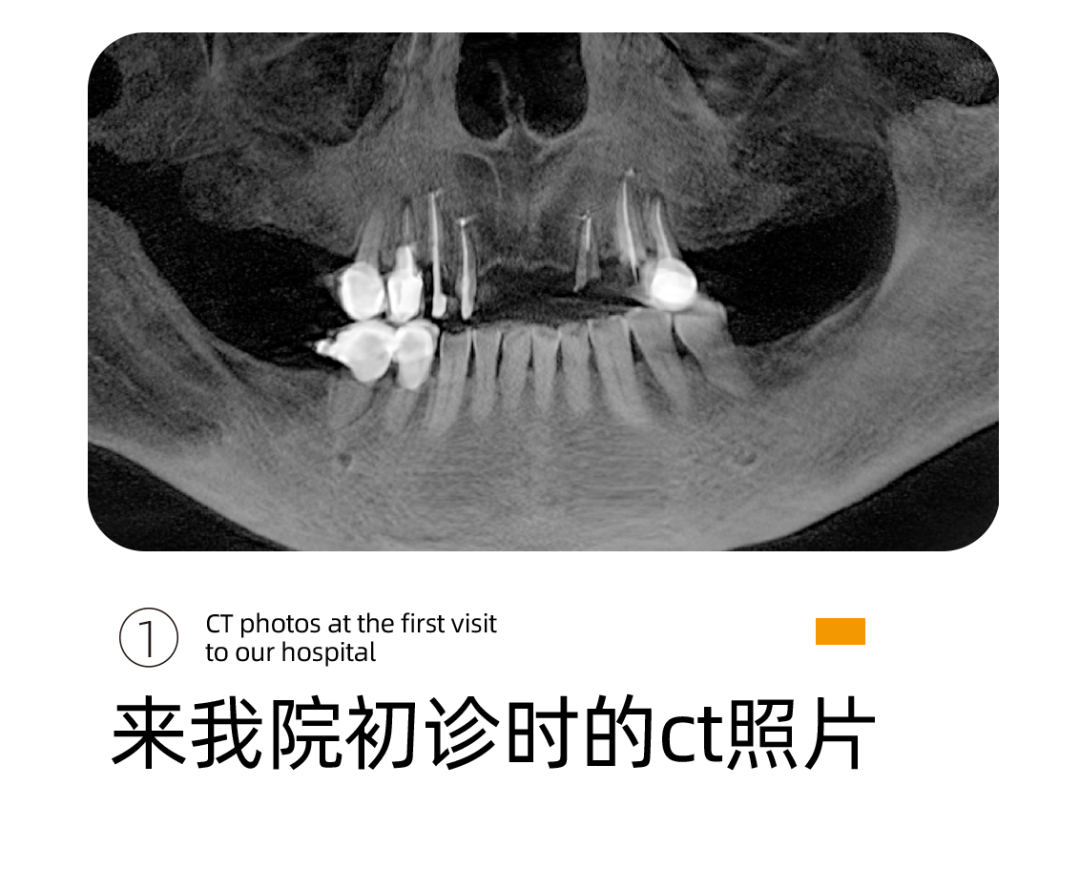

针对阿姨的情况,李雪松院长为阿姨指定全套的数字化种植方案。

什么是UNIC数字化种植方案呢?

其实就是借助Sirona CBCT全景影像信息和相关修复信息为基础,借助数字化专业种植设计软件进行术前诊断和种植方案规划。

通过数字化种植手术导向模板,将术前制订的种植方案准确应用于种植手术和即刻修复的全过程,实现以修复为导向的牙种植修复。

换句话说,运用数字化种植技术就是让所有种植操作可以直观得看到,并且能够看得懂。

它的优势在于种植医生借助数字化设备可以真正实现以修复为导向的种植理念,并且实际运用到临床操作中,实现微创种植,不翻瓣,将创口降到最低。

全数字化导板设计会依靠自身数字化的精确定位和微创特点,大大减少失误操作,提高种植手术的精准度。